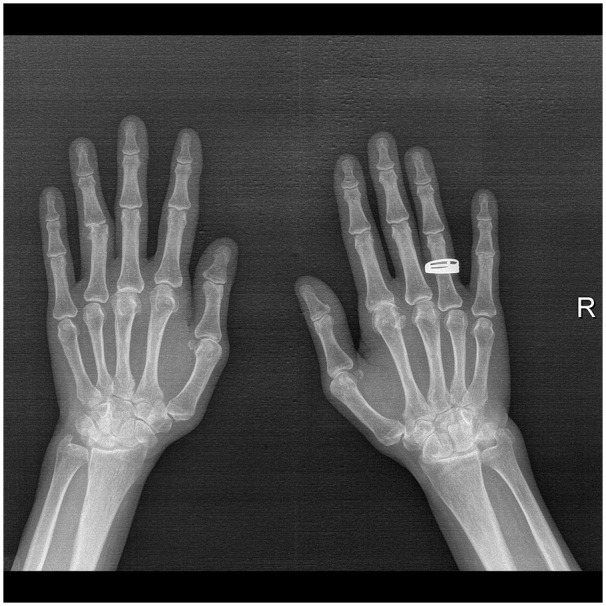

Quadricuspid aortic valve is a very rare congenital anomaly. Its association with rheumatoid arthritis is exceptional with this being the third case reported in the literature. We report a case of a 52 year old female patient with quadricuspid aortic valve type C accompanied by moderate to severe aortic regurgitation and longstanding, advanced form of rheumatoid arthritis. Having refused surgical aortic valve intervention 4 years ago, the patient is currently under a watchful follow-up strategy. The patient received a diagnosis of rheumatoid arthritis over 15 years before and presently has serious deformities in the hands, legs, feet, and spine. In conclusion, quadricuspid aortic valve and rheumatoid arthritis together are extremely rare. While it is possible that this association is coincidental, considering the genetic background of both disorders, there is a potential for them to be interconnected comorbidities. This report is the first to highlight the association between the 2 disorders.

四尖瓣主动脉瓣是一种非常罕见的先天性畸形。它与类风湿性关节炎的关系非常特殊,这是文献中报道的第三例。我们报告了一例 52 岁女性患者的病例,她患有四尖瓣主动脉瓣 C 型,伴有中重度主动脉瓣反流和长期晚期类风湿性关节炎。4 年前,患者拒绝接受主动脉瓣手术治疗,目前正处于观察随访阶段。患者在 15 年前被诊断出患有类风湿性关节炎,目前手、腿、脚和脊柱严重变形。总之,四尖瓣主动脉瓣和类风湿性关节炎同时出现的情况极为罕见。虽然这种关联可能是巧合,但考虑到这两种疾病的遗传背景,它们有可能是相互关联的合并症。本报告首次强调了这两种疾病之间的关联。